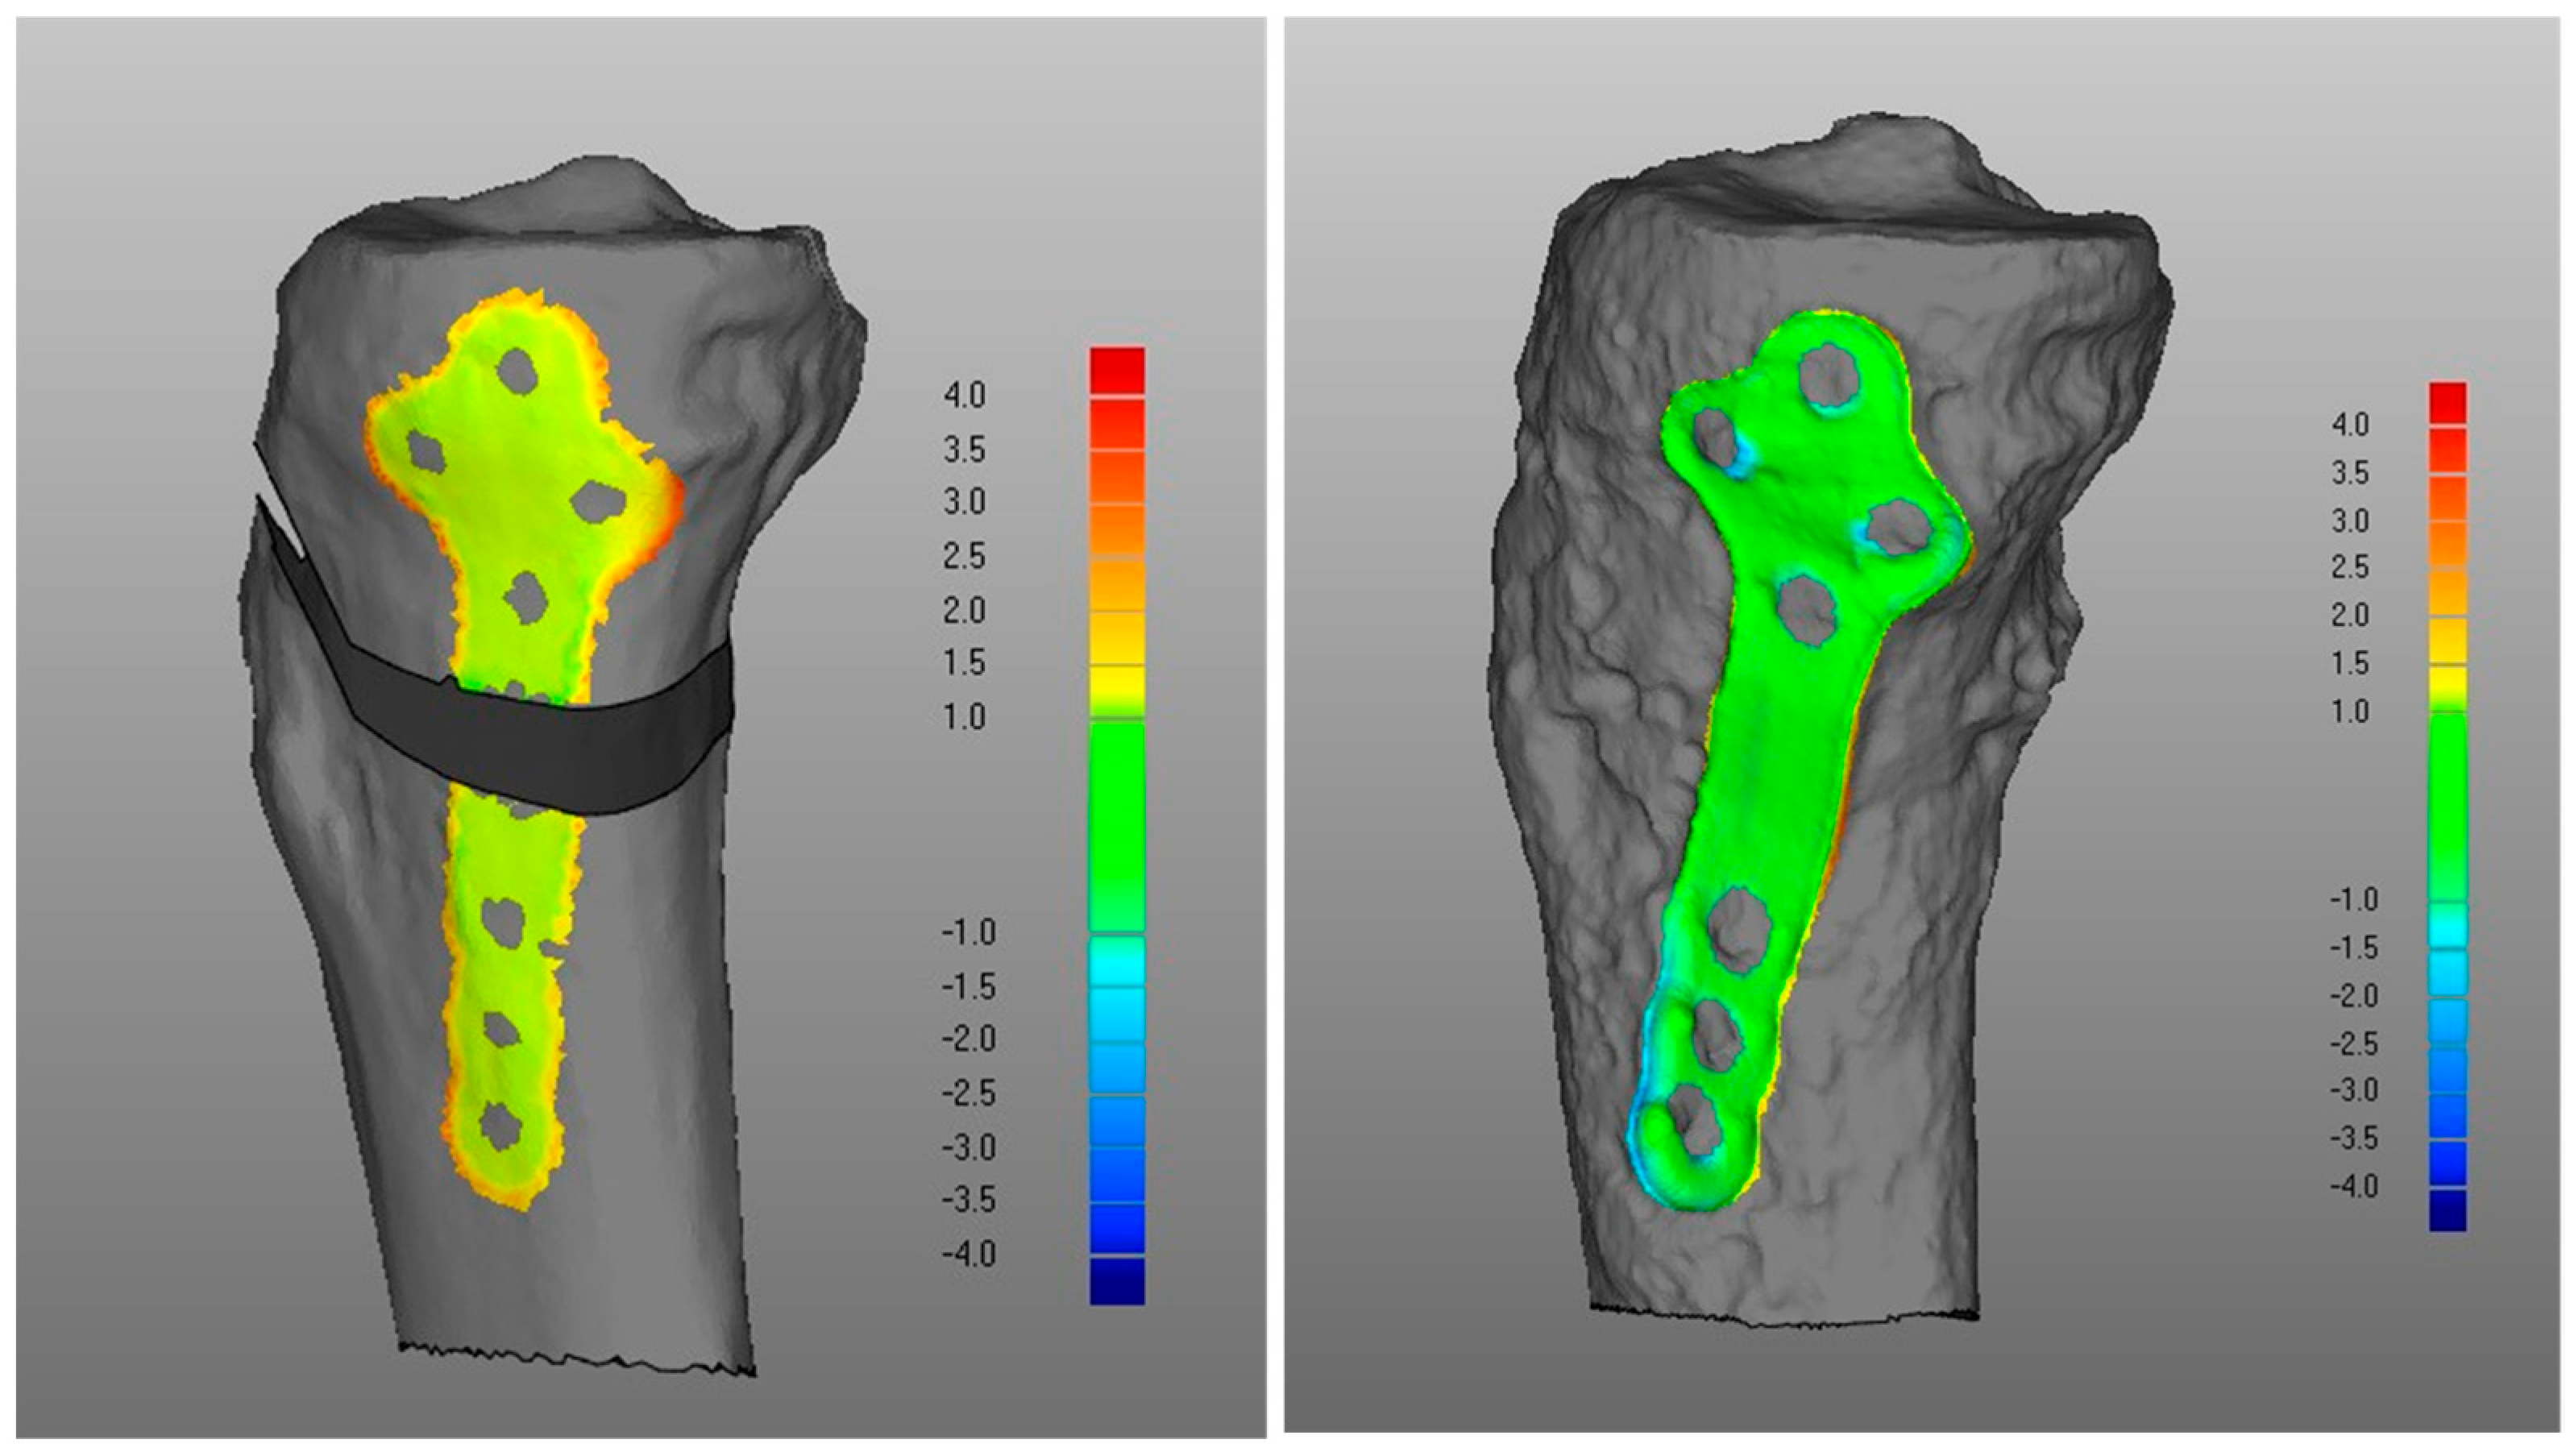

- Overall, a good replication of PLA tibia morphology was achieved in POST (Figure 3 and Figure 4), with average values for of 1.4 mm and of −0.9 mm, associated with very small DMA standard deviation (DSD average value 1.6 mm) over the entire patient cohort (Table 1). Most points were in the safe zone (Table 2), although discrepancies were observed, mainly due to the difficulty of excluding the bone allograft (used to fill the osteotomy cut which is the standard practice of the operating surgeon) during image segmentation, thus altering the morphology of the area around the osteotomy in POST with reference to the corresponding one in PLA.Table 1. DMA outputs (units for all variables mm). = Positive mean Distance, = Negative mean Distance, DSD = DMA standard deviation.Table 1. DMA outputs (units for all variables mm). = Positive mean Distance, = Negative mean Distance, DSD = DMA standard deviation.

DMA Comparison Variable Mean Median Standard Deviation (i) POST tibia vs. PLA tibia 1.4 1.4 0.5 −0.9 −0.8 0.4 DSD 1.6 1.4 0.5 (ii) POST plate vs. PLA plate 0.4 0.4 0.1 −0.2 −0.2 0.1 DSD 0.4 0.4 0.1 (iii-a) PLA plate vs. PLA tibia 1.3 1.3 0.2 0 0 0 DSD 0.5 0.4 0.2 (iii-b) POST plate vs. POST tibia 0.7 0.6 0.4 −0.3 −0.3 0.2 DSD 0.6 0.5 0.2 (iv) POST tib plateau vs. PRE tib plateau 0.4 0.4 0.2 −0.3 −0.2 0.1 DSD 0.6 0.6 0.2 Figure 3. Boxplots for positive mean distance (), negative mean distance (), and DMA standard deviation (DSD) for all sets of surface comparisons.Figure 3. Boxplots for positive mean distance (), negative mean distance (), and DMA standard deviation (DSD) for all sets of surface comparisons.Figure 4. Screenshot of DMA software depicting (i) POST tibia versus PLA tibia. Data from a representative case, the colour scale gives surface deviation in millimetres.Figure 4. Screenshot of DMA software depicting (i) POST tibia versus PLA tibia. Data from a representative case, the colour scale gives surface deviation in millimetres. - (ii)

- Regarding the matching of the plate surface contour to the tibia, the comparison between PLA, i.e., iii-a (Figure 6 left), and POST, i.e., iii-b (Figure 6 right), the low DMA values (Figure 3 and Table 1) reveal a very good replication of the planned contour matching of the plate to the tibia in the POST condition. In iii-a comparison, there was no negative value, i.e., penetration, of the test surface relative to the reference (Table 2).